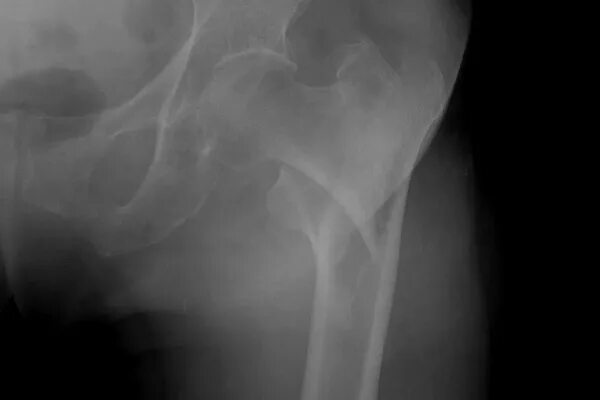

Чрезвертельный перелом без операции